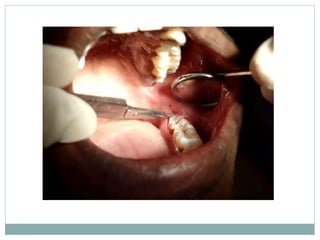

Clinical Applications in Periodontics

 Initial non-surgical

pocket therapy.

 Frenectomy.

 Gingivectomy.

 Soft tissue grafting.

 De-epithelialization of

the gingival margin.

 Gingival troughing.

 Removal of granulation

tissue.

 Osseous recontouring.

 Crown lengthening.

 Second stage surgery-

implants.

 Peri-implantitis.

 Operculectomy.